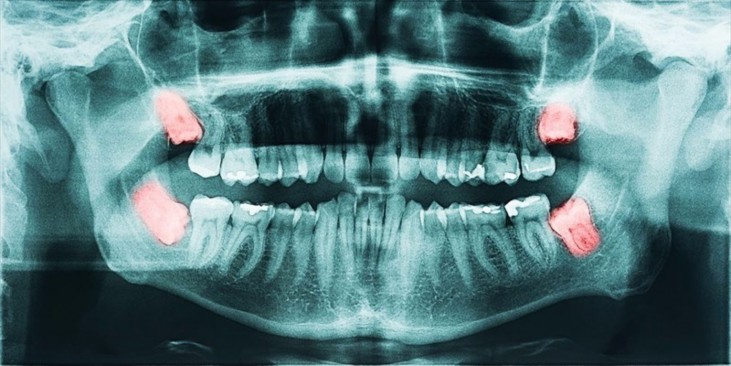

A wisdom tooth may get stuck or develop at an angle if there is not enough space to come through usually, we call this an impacted wisdom tooth.

If a wisdom tooth doesn’t come in properly or there isn’t enough room in your mouth, it can cause complications.

Impacted wisdom teeth can cause infection, pain, inflammation and other issues.

Dentists may recommend the removal of wisdom teeth as a precaution because they can cause long-term problems, like:

- Developing tooth decay or gum disease

- If wisdom teeth are impacted, you may develop and infection around the gum

- It may harm nearby teeth

- The impacted tooth may have a build-up of bacteria and plaque around it

- In rare cases, before the tooth erupts, there’s a possibility that the sack of tissue around the tooth can grow into a cyst.